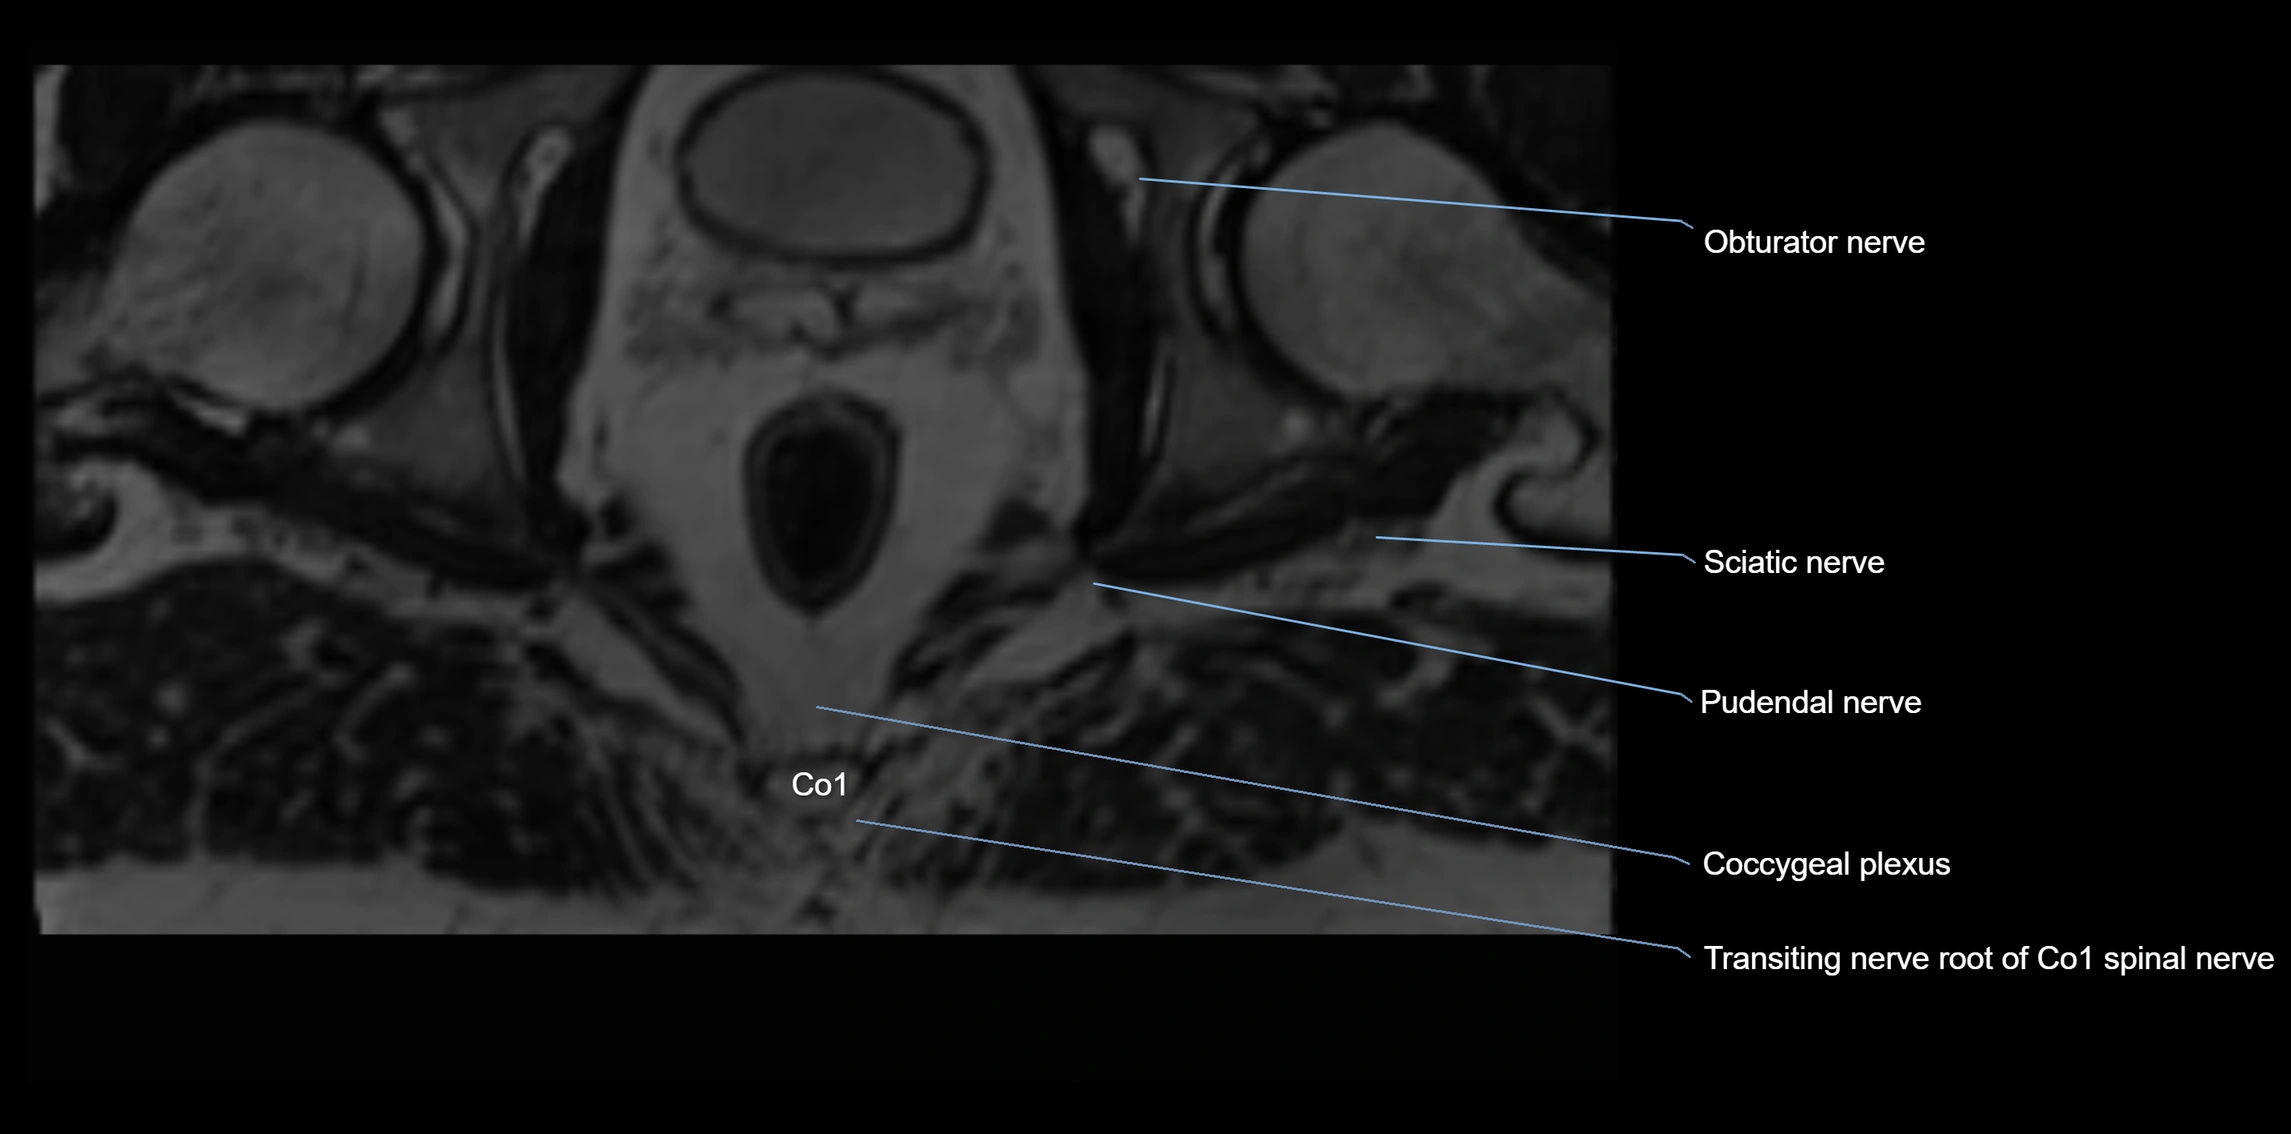

MRI Appearance

T1-weighted images:

• Nerve appears as a very thin low-to-intermediate signal intensity structure

• Surrounded by bright fat, aiding visualization

T2-weighted images:

• Nerve shows intermediate to mildly hyperintense signal compared to muscle

• Pathological involvement appears brighter

STIR (Short Tau Inversion Recovery):

• Normal nerve appears dark

• Inflamed or entrapped nerve appears bright hyperintense

T1 Fat-Sat Post-Contrast:

• Normal nerve enhances minimally

• Pathologic nerve (neuritis, entrapment, tumor infiltration) shows focal or diffuse enhancement

3D T2 SPACE / CISS:

• Nerve appears intermediate to mildly hyperintense compared to muscle

• Surrounded by bright fat or CSF, improving visualization

• Best sequence for mapping small pelvic nerves such as the anococcygeal

MRI image

image